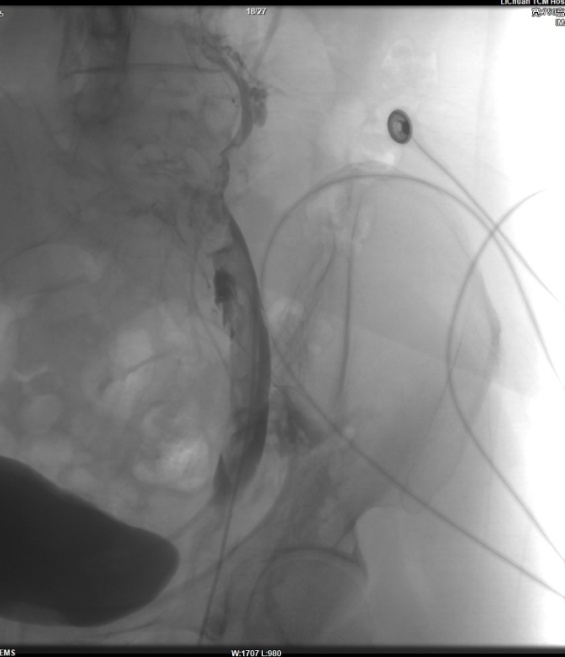

术前DSA造影:左髂静脉狭窄并下肢静脉多发血栓,伴侧支循环形成。